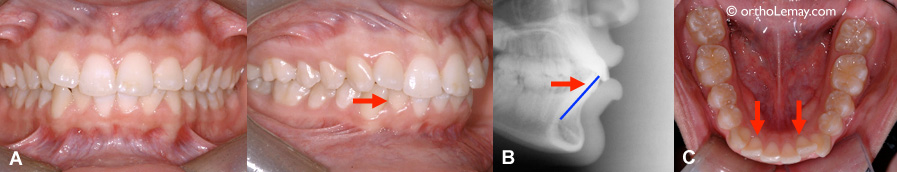

Voici un exemple de la façon dont la nature tente de compenser pour un déséquilibre entre les mâchoires pour une malocclusion de type classe 3 non traitée. (A) La mandibule étant légèrement forte et/ou le maxillaire déficient, les incisives supérieures sont inclinées vers l’avant tandis les incisives inférieures sont basculées vers l’intérieur. (B) incisives inférieures inclinées vers l’intérieur.

(A) Malocclusion classe 2 (non traitée) avec décalage modéré entre les mâchoires. Il y a peu d’écart entre les incisives supérieures et inférieures car les incisives inférieures sont inclinées vers l’avant dans une tentative de compensation naturelle. (B) Radiographie montrant l’inclinaison des dents. (C) Incisives inférieures inclinées.